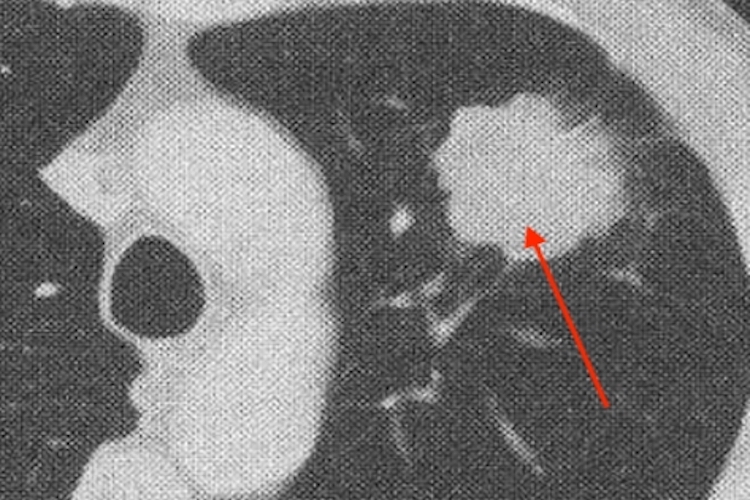

周围型

早期周围型肺癌可清晰显示肿瘤内部特征、边缘情况及周围征象。周围型肺腺癌较小时可表现为磨玻璃结节或实性结节。中晚期周围型肺癌较X线更敏感,能更清晰地显示结节与肿块的细节。增强扫描时,肿块可呈较明显的均匀或不均匀强化。